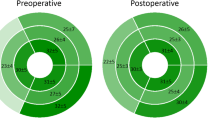

Figure 2 shows the Kaplan–Meier curves. In CCTGA and TGA, patients with significant intradyssynchronous RV showed poor event-free survival rates (log-rank test P = 0.004 and P = 0.04).

In CCTGA, the cut-off value of the maximum time difference for the intraventricular peak systolic strain was 110 ms (P < 0.001; AUC, 0.81; sensitivity, 77.8%; and specificity, 80.0%), and that for the interventricular peak systolic strain was 131 ms (P < 0.0001; AUC, 0.88; sensitivity 88.9%; and specificity, 81.8%) in the 4-chamber view. In the short-axis view, the cut-off value of the maximum time difference for the intraventricular peak systolic strain was 121 ms (P < 0.003; AUC, 0.82; sensitivity 75.0%; and specificity 85.7%). In TGA, the cut-off value of the maximum time difference for the intraventricular peak systolic strain was 110 ms (P < 0.002; AUC 0.78; sensitivity, 67.0%; and specificity, 79.0%) in the short-axis view.

In patients with CCTGA, the important predictions for major cardiac events were NYHA FC, RV volume, longitudinal early diastolic SR, and intra- and inter-ventricular dyssynchrony (Table 3). GLS also showed a tendency to be predictive (P = 0.07), but this was not statistically significant. In patients with TGA, age, NYHA FC, QRS duration, RV volume, RV mass index, LV volume, GLS, GCS and intradyssynchrony in the short-axis view, were important predictive factors for major cardiac events. Intraventricular dyssynchrony in the four-chamber view and interventricular dyssynchrony also showed a tendency to be predictive (P = 0.07 and 0.08), but this was not statistically significant.